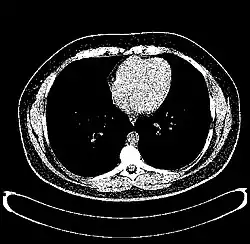

The Hounsfield scale (/ˈhaʊnzfiːld/ HOWNZ-feeld), named after Sir Godfrey Hounsfield, is a quantitative scale for describing radiodensity. It is frequently used in CT scans, where its value is also termed CT number.

HU-based differentiation of material applies to medical-grade dual-energy CT scans but not to cone beam computed tomography (CBCT) scans, as CBCT scans provide unreliable HU readings.[7]

Values reported here are approximations. Different dynamics are reported from one study to another.

Exact HU dynamics can vary from one CT acquisition to another due to CT acquisition and reconstruction parameters (kV, filters, reconstruction algorithms, etc.). The use of contrast agents modifies HU as well in some body parts (mainly blood).

A practical application of this is in evaluation of tumors, where, for example, an adrenal tumor with a radiodensity of less than 10 HU is rather fatty in composition and almost certainly a benign adrenal adenoma.[31]